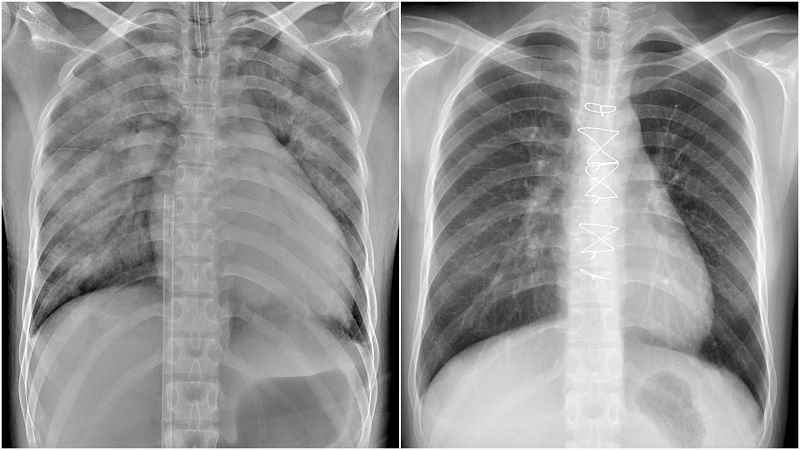

鄭小姐裝上葉克膜六小時後,胸腔X光影像中肺部幾乎呈白色,肺水腫嚴重且心臟明顯擴大。(右圖)鄭小姐出院後第二次回診檢查,胸部X光影像顯示肺部與心臟已恢復正常。.jpg)